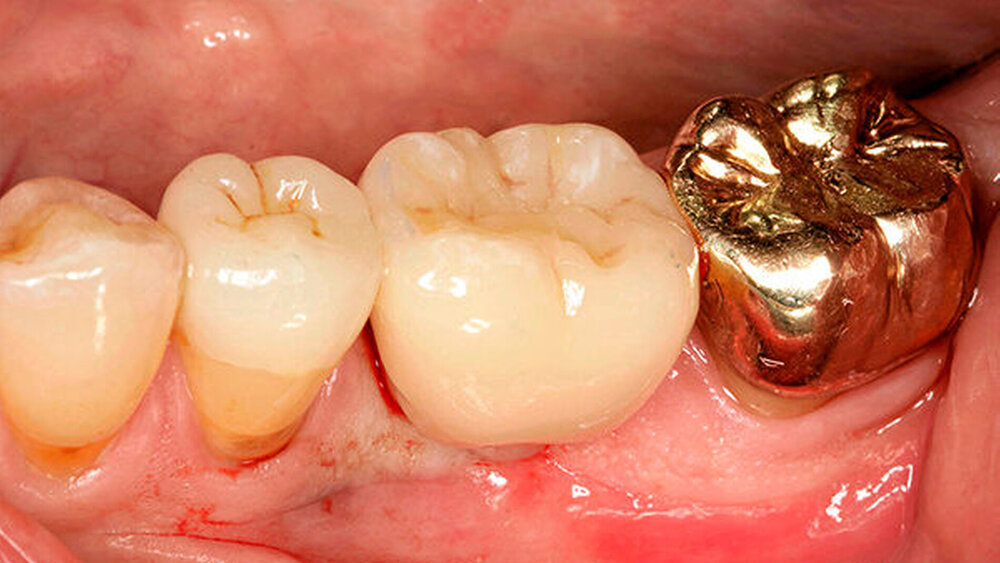

Auf jeden Fall! Neben einer besseren Ästhetik, gerade bei der Verwendung von Zirkon, ist die Lage des Übergangs Abutment-Krone bei zementierten Arbeiten von enormer Wichtigkeit. Werden aufgrund zu tief subgingival liegender Kronenränder Zementreste unzureichend entfernt, stellt dies eine der Hauptursachen für eine frühe Periimplantitis dar.